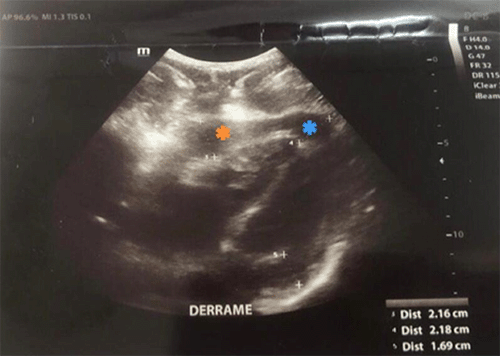

We present the case of a 19-year-old male who suffered a single stab wound to the left anterior chest at the fourth intercostal space with moderate bleeding from the site of injury. His initial blood pressure (BP) was 120/65, heart rate (HR) of 53, respiratory rate (RR) of 30, oxygen saturation of 93%, temperature of 36.4°C, and Glasgow Coma Scale (GCS) of 15. Focused assessment with sonography for trauma (FAST) examination demonstrated pericardial effusion (22 mm thickness) (Figure 1). Admission hemoglobin was 14.6. Based on the FAST findings, the patient was taken to the operating room for a subxiphoid pericardial window (SPW). Several blood clots and approximately 50cc of serosanguinous fluid were evacuated (Figure 2). A number 12 Nelaton catheter was placed in the pericardial space, and lavage of the space with 2000 ml of warm normal saline was performed (Figure 3). After lavage, the returned fluid was clear. The incision was closed, and the patient was transferred to the recovery room in stable condition. A repeat echocardiogram on postoperative day 1 showed normal cardiac function, and the patient was discharged home that evening.

Figure 1. Preoperative Echocardiogram Demonstrating Pericardial Effusion (Indicated by *). Published with Permission